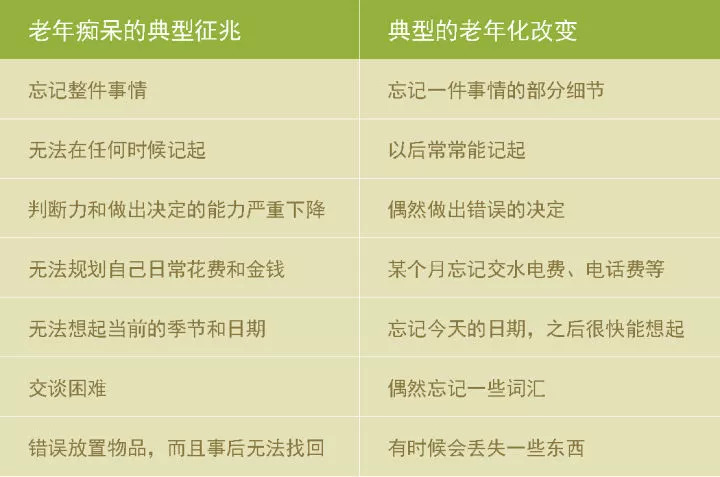

需要注意的是,年龄大了会有一些衰老的症状,但是不一定就是阿尔茨海默病,表格可供参考。